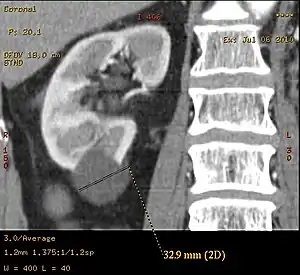

Renal cyst

A renal cyst is a fluid collection in or on the kidney. There are several types based on the Bosniak classification. The majority are benign, simple cysts that can be monitored and not intervened upon. However, some are cancerous or are suspicious for cancer and are commonly removed in a surgical procedure called nephrectomy.

Bosniak II cyst at the lower pole of right kidney with septations within.